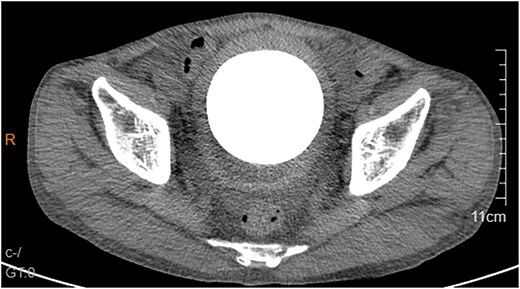

A 53-year-old male, presented to a local hospital in April 2021 due to lower back discomfort. There was no weight loss, fatigue, fever, or other systemic symptoms. Urinalysis showed leukocytes (+++); computed tomography (CT) revealed a 76 × 74 mm stone, bladder wall thickening, and dilation of the bilateral renal pelvis and ureters (Fig. 1). Subsequently, he underwent pubic bladder incision for stone removal and bladder diversion at that hospital. Postoperatively, the incision site was swollen, exuding fluid, and did not heal over an extended period. A total of 14 months after the initial surgery, he was admitted to our hospital. On examination, there was excessive granulation tissue proliferation around the bladder incision wound and near the bladder diversion tube, with surface exudation and easy bleeding upon touch (Fig. 2). Upon admission, urinalysis showed leukocytes (++), occult blood (++), glucose (++), and protein (++). Postprandial blood glucose level was 19.58 mmol/l. Urine culture indicated tropical pseudo-filamentous yeast and Enterococcus. Secretion culture showed E. coli and Klebsiella pneumoniae subsp. Blood routine test indicated white blood cell count and highly sensitive C-reactive protein within normal ranges. He received infection control, glucose management, and wound care, but the wound did not heal. Abdominal CT and pelvic magnetic resonance imaging (MRI) revealed bladder wall thickening and soft tissue in the anterior pelvic area (Fig. 3). Histopathological results from abdominal wall tissue biopsy indicated moderately differentiated squamous cell carcinoma. Immunohistochemistry indicated: CK(pan)(+), CK20(−), CK7(−), PAX-8(−), GATA3(−), P63(+), P53(+), Ki-67(+) at 40% (Fig. 4).

Abdominal CT showed a massive bladder stone measuring 76 × 74 mm, thickened bladder walls.